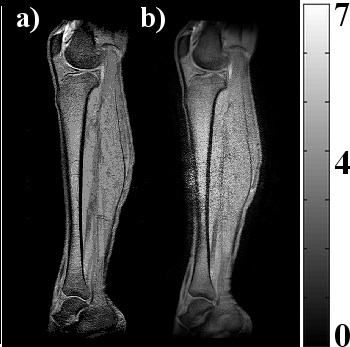

Another possible source of error is the image reconstruction scheme which is not the best suited for twMRI experiments. This is a matter of concern and deserves a thorough investigation. However, the performance of the travelling-wave approach shows a great potential for imaging large FOVs. The images in Fig. 9.a) and b) were normalized to the standard deviation of the image for comparison purposes and shown in Fig. 10. Comparison plots of image intensity distributions were also computed using the image data from Fig. 9 for both images. Fig. 9.c) image was shows very poor image quality and it was not used in the image comparison.

[Uncaptioned image]

Figure 10. Comparison of normalized images acquired with the whole-body birdcage coil (a) and PPWG + pair of RF coils (b). Central region of (b) image is greater that the other leg image. Noise is probably due to the fold over effect and that no fold over suppression was applied.

Fig. 11 shows the distribution forms for both directions. The waveguide-acquired profile and the birdcage coil-acquired image show a pretty similar performance. The Fig. 4.b) simulation agrees very well with the experimental results shown in Fig. 11.b) for the PPWG-acquired image. In our study, the experimental and numerical results show that the restriction of a 7T/60 cm system is removed, allowing this approach to be used in a wider variety of applications involving imagers with much smaller magnet bores. The PPWG most likely has the simplest waveguide configuration available, allowing the travelling-wave approach to be implemented easily. It is much easier to build a waveguide like this and use standard surface RF coils to excite travelling-waves in a magnet bore. We suspect that by operating the coil array in the transceiver mode, the image SNR will be improved.

Figure 11. Comparison plots of normalized SNR distributions of Fig. 10 images, profiles were taken across the brown line (a) and along the red line (b) in the leg image. These profiles show a pretty similar pattern and performance. A strong concordance can be observed in (b) PPWG profiles with the B1 simulation profiles of Fig. 5.a).